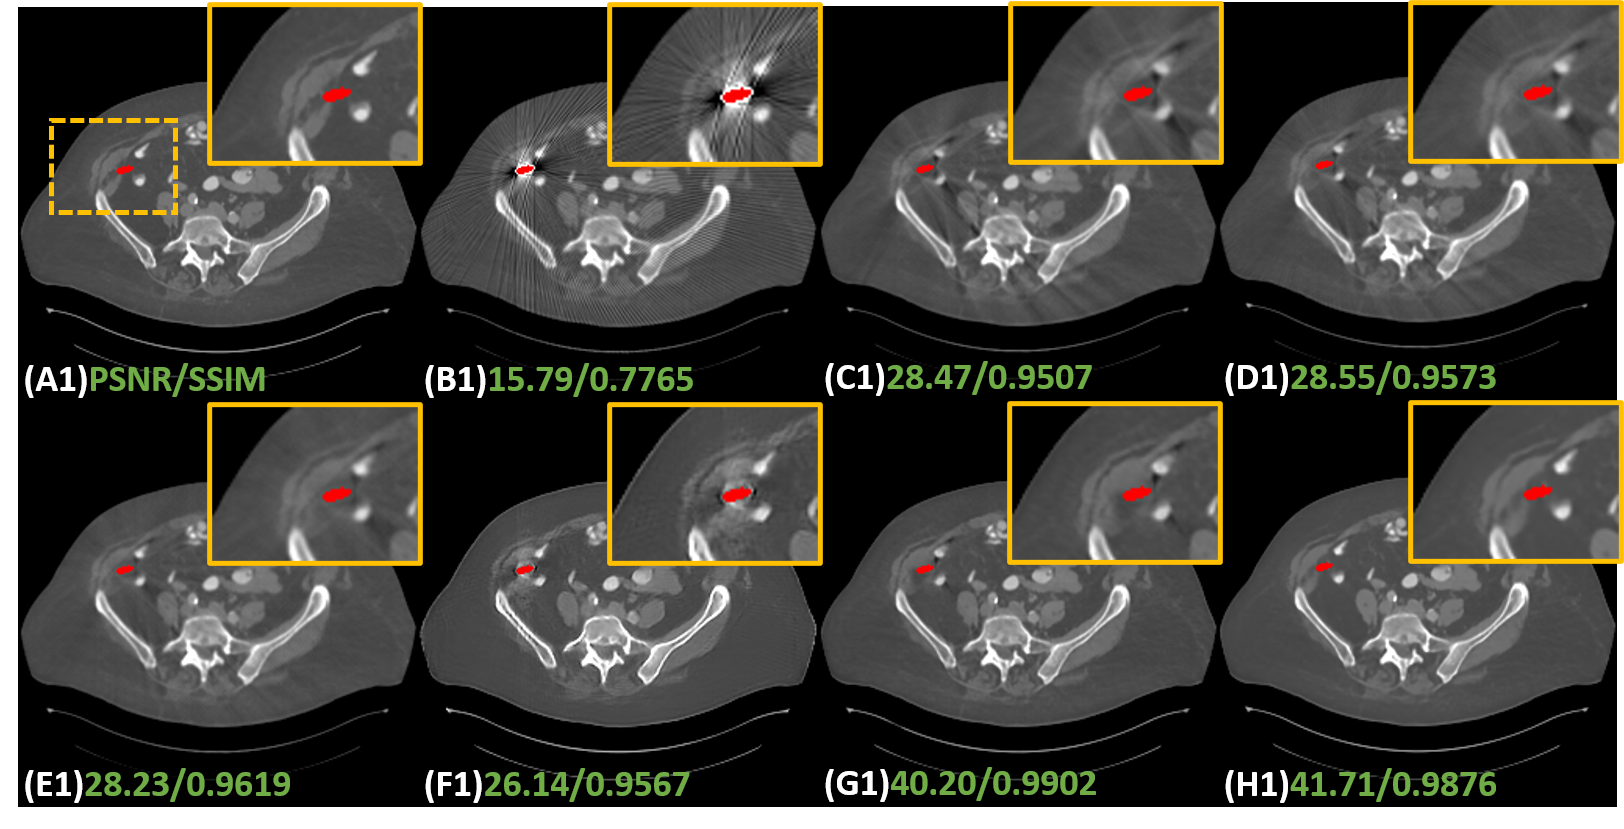

To validate the effectiveness of the proposed IDOL-Net, several methods, including LI [9], NMAR [16], CNNMAR [37], ADN [12], DuDoNet [13] were involved for comparison. LI and NMAR are widely used interpolation-based methods. CNNMAR takes advantage of the outputs of different MAR methods to generate a prior image. ADN is an advanced unsupervised image-domain method. DuDoNet is a state-of-the-art dual-domain approach. All the methods were implemented with the publicly released code or strictly implemented according to the original paper. Structural similarity (SSIM) and peak signal to noise ratio (PSNR) were employed as the quantitative metrics.

1) Quantitative comparisons: Table 1 shows the average quantitative results on the simulated dataset. It is observed that all the methods can significantly improve the PSNR and SSIM values and DL-based methods achieve better scores than traditional MAR methods. DuDoNet and IDOL-Net gain obvious improvements in terms of both metrics, which quantitatively demonstrated the merits of dual-domain methods. In addition, our method produces a noticeable advantage over DuDoNet in terms of both metrics for all the metal sizes, with an average improvement of 3.3dB in PSNR and 0.81 in SSIM.

2) Qualitative comparisons: Fig. 6 shows the representative results of different methods on simulated data with different metal sizes. For better visualization, the metal masks are painted in red. Due to the fact that LI and NMAR are interpolation-based methods directly discarding the projection data in metal trace, the metal information is lost and the corrected sinogram cannot keep the continuity at the boundaries of metal trace, leading to blurred tissues around the metals and remarkable secondary artifacts. Although CNNMAR fuses the results of different MAR methods, the improvement is quite limited. ADN achieves better performance on structure recovery around the metal implants than LI, NMAR and CNNMAR, and even DuDoNet in some cases, but it also can be noticed that in the second case (Fig. 6 (F2)), the shadow artifacts are not well suppressed and the details covered by the artifacts are hard to identify. This phenomenon probably lies in that ADN is essentially a post-processing method, which does not leverage the sinogram information. Compared to other methods, DuDoNet and the proposed IDOL-Net have the best performance on artifact reduction, but DuDoNet cannot recover the structures and tissues around the metal well, which can be clearly observed in the magnified yellow boxes in Fig. 6 (G2) and (G3). Our proposed IDOL-Net not only effectively removes most artifacts but also recovers the details better than all the other methods in all cases.